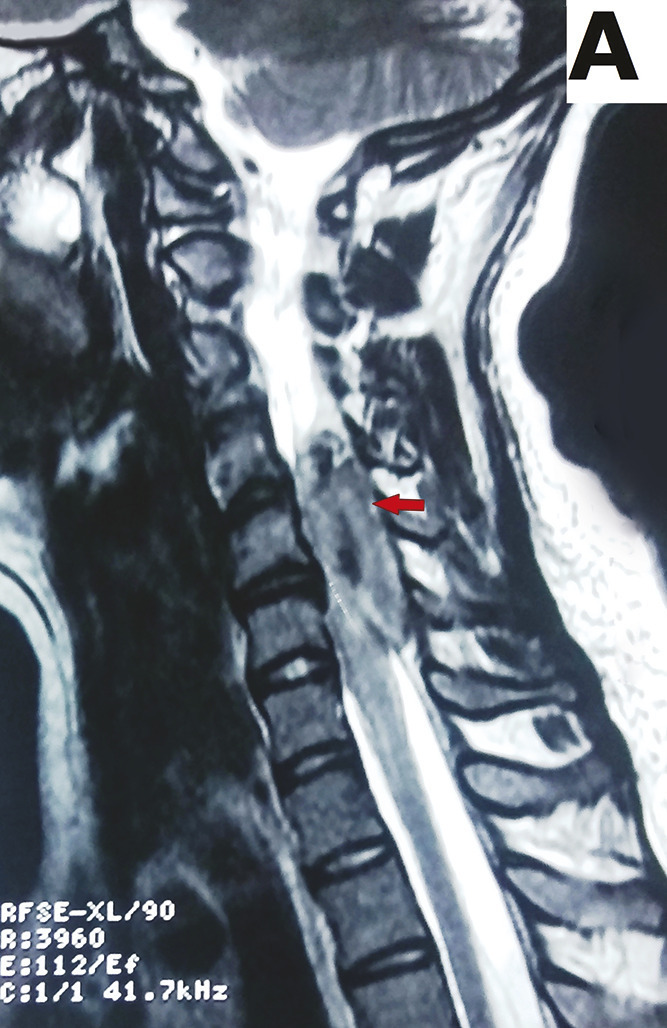

Cette femme de 35 ans, enceinte de 20 semaines, avait une tétraplégie d’installation brutale, un syndrome tétrapyramidal et des troubles sphinctériens à type d’incontinence urinaire et anale. L’imagerie par résonance magnétique (IRM) cervicale montrait une lésion extramédullaire extradurale étendue de C3 à C6, un iso-signal en séquence pondérée T1 et en hypersignal T2 (fig. 1 ) ; sur l’injection de gadolinium, on notait la limite entre la dure-mère et la lésion. Le diagnostic de compression médullaire aiguë liée à un hématome épidural était retenu. Une décompression chirurgicale était réalisée (fig. 2 ). L’évolution était marquée par une amélioration partielle de la symptomatologie, et l’IRM cervicale de contrôle montrait une disparition de l’hématome.